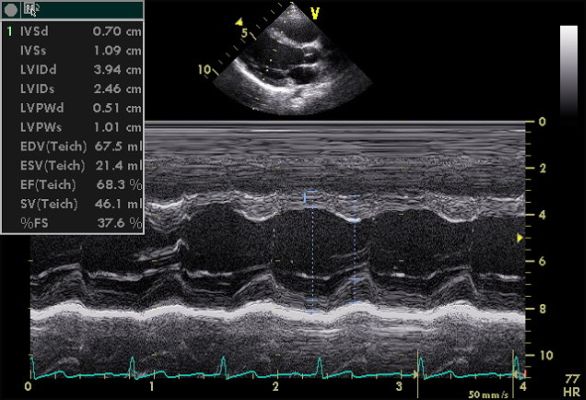

2D & Color Doppler Echo

2D Echo with Doppler is an examination that is performed on the ultrasound machine to detect abnormalities of the heart. It is used in many situations to detect cardiac function and ejection, valve motion, as a pre operative fitness test, to look for fluid around the heart, and motion abnormalities.